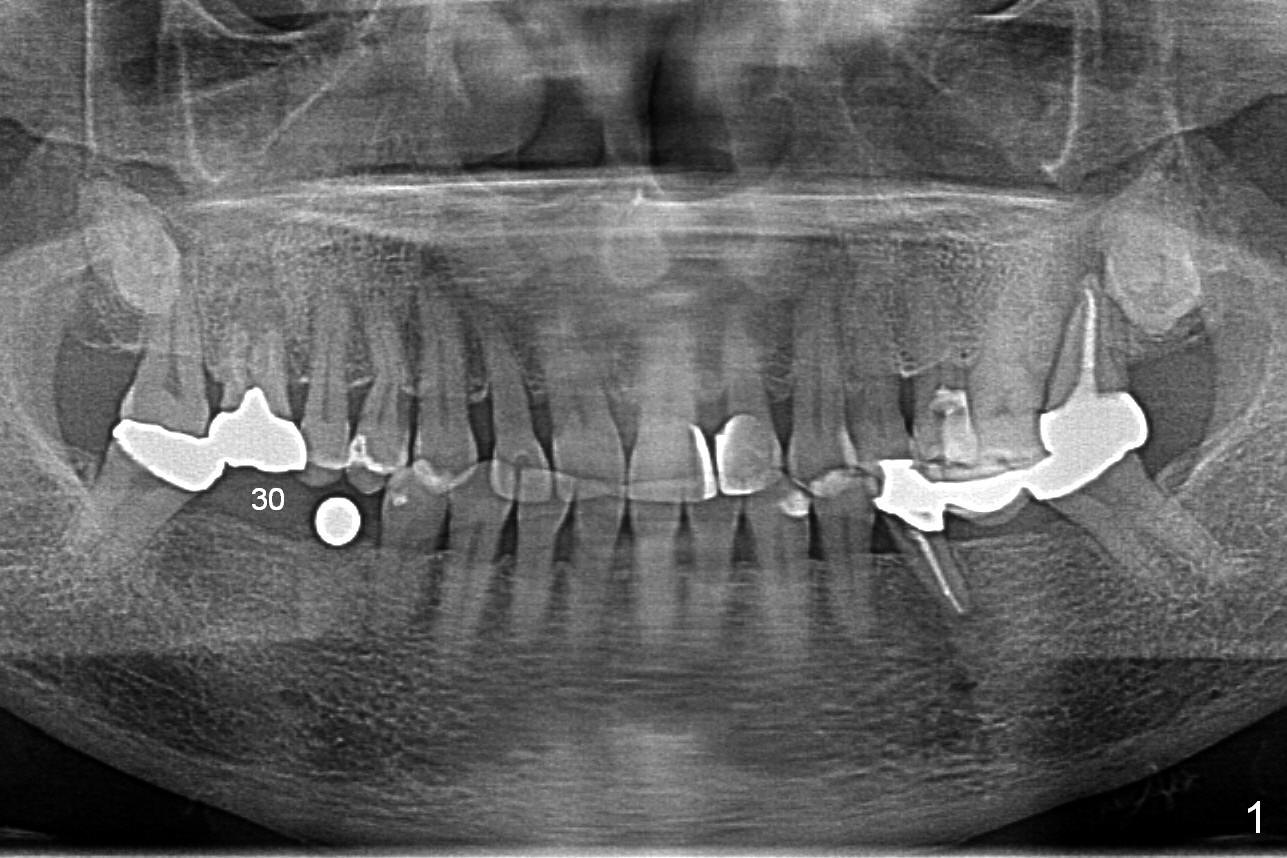

A 64-year-old woman requests implant placement at #29 and 30. There appears to be bone graft at the site of #29 (Fig.1). The ridge at these sites is moderately atrophic. The diameters of the implants will be determined by using Implant Positioners. Use Magic Split if needed. To avoid the Inferior Alveolar Nerve and Mental Nerve (Fig.2 red dashed line), initial depths at #29 and 30 are 10 and 12 mm.

The ridge appears to be not so narrow (Fig.3). The opposing teeth (#3-5) are slightly supraerupted (Fig.4).